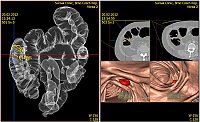

V SurGal Clinic provádíme neinvazivní vyšetření tlustého střeva na nejmodernějším 64řadém CT stroji Toshiba Aquilion vybaveném speciální rekonstrukční pracovní stanicí Vitrea.

CT virtuální kolonoskopieumožňuje virtuální pohled a pohyb luminem tlustého střeva v celé jeho délce po dostatečné rozepnutí tleustého střeva vzduchem nebo oxidem uhličitým.

Pro polypy velikosti 1 cm a více dosahuje senzitivita a specificita 90-100 %, pro polypy velikosti 5-9 mm 60-75 % a pro polypy velikosti menší než 5 mm je senzitivita a specificita pouze asi 25 %. Hlavní snahou tohoto vyšetření je tedy zachytit polypy větší než 5 mm, které již pro pacienta mohou do budoucnosti znamenat určité riziko a pacienta s tímto nálezem dispenzarizovat. Při porovnání „klasické“ endoskopické kolonoskopie a virtuální kolonoskopie má právě virtuální kolonoskopie celou řadu nepopiratelných výhod: